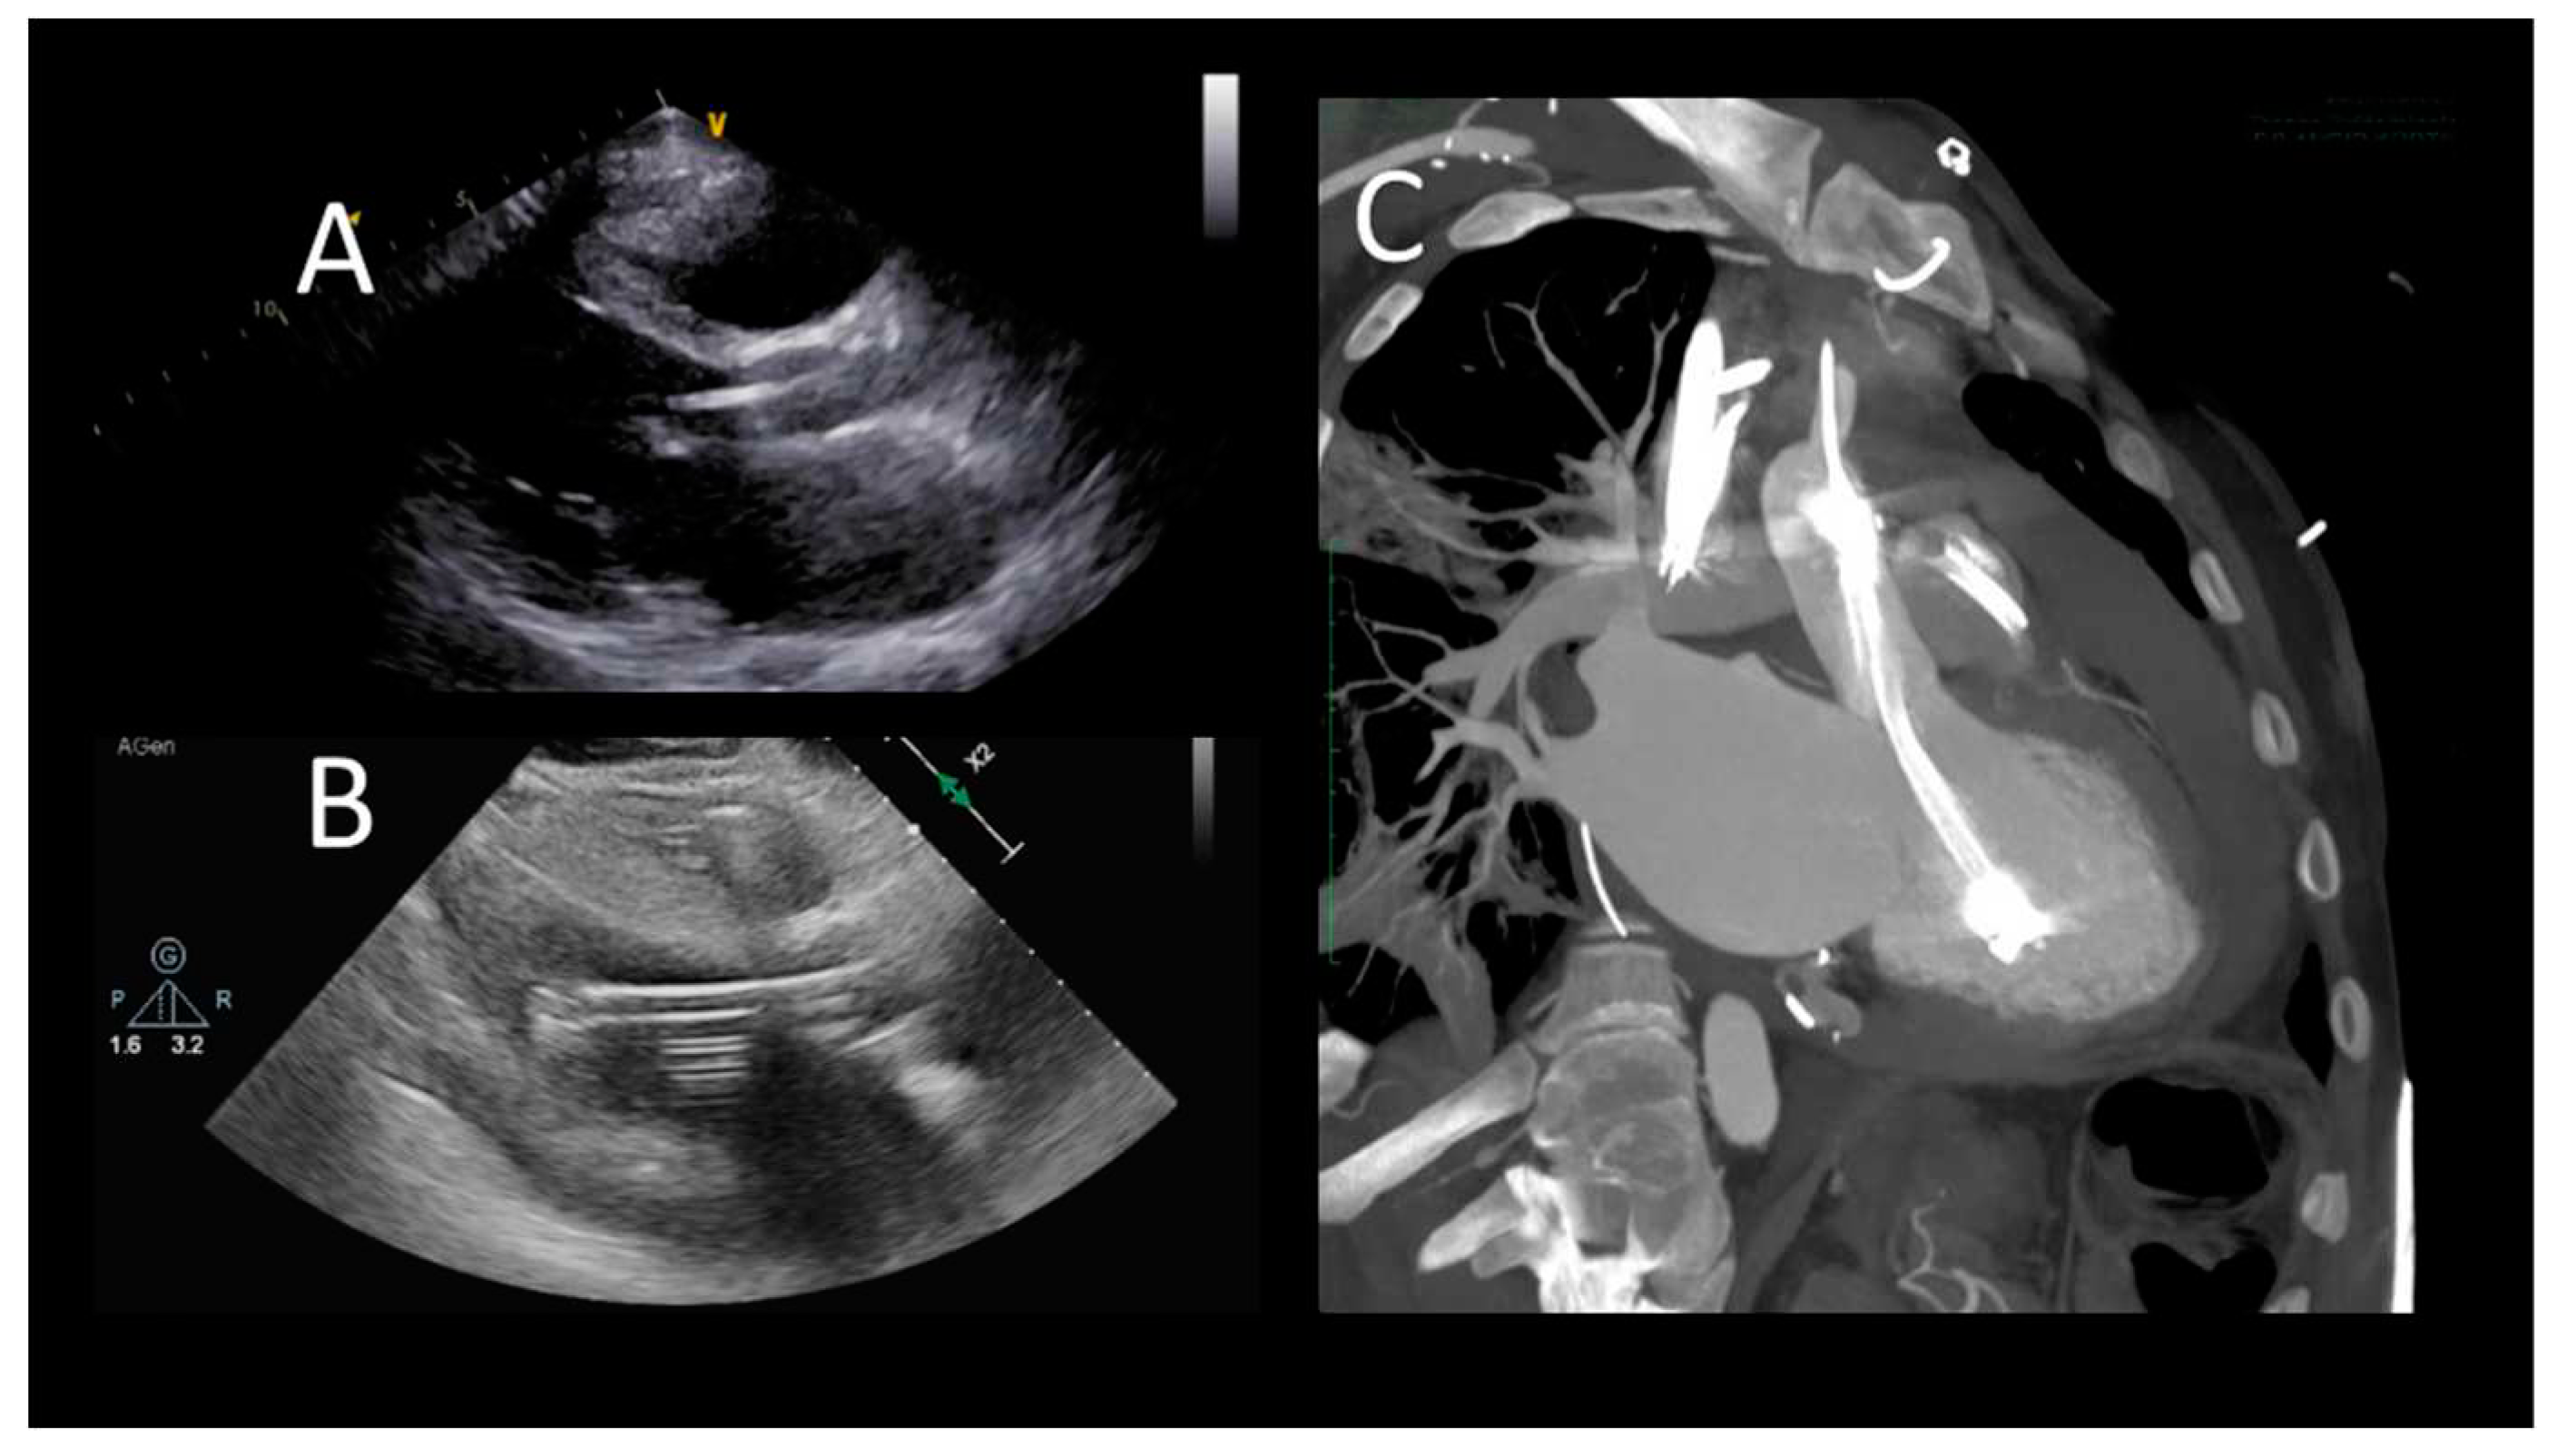

As for IABP, Impella devices are commonly placed under fluoroscopic guidance, but in patients with refractory shock, preventing transportation of the patient to the cardiac catheterization laboratory, TEE can help bedside positioning of the device (32). One single centre study demonstrated no difference in Impella-related complications when comparing TEE alone guided placement with the fluoroscopic guided cohort (33). The mid-esophageal long-axis and 4-chamber views can be used to visualize the guidewire crossing the aortic valve. The catheter should be oriented towards the ventricular apex. TEE can also confirm the absence of iatrogenic aortic dissection from the procedure (32). Both TTE and TEE are helpful in identifying correct positioning of the Impella device (Figure 2).

Figure 2. Transthoracic echocardiographic evaluation after Impella implantation A) correct device's position; B) uncorrect position (towards the LV apex), C) CCT showing incorrect, apical position.